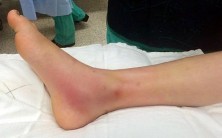

A 13-year-old girl sustains an ankle injury during a soccer match. Radiographs reveal an isolated Salter-Harris III fracture of the anterolateral distal tibial epiphysis (Tillaux fracture). Which of the following describes the anatomical sequence of distal tibial physeal closure that predisposes adolescents to this specific fracture pattern?